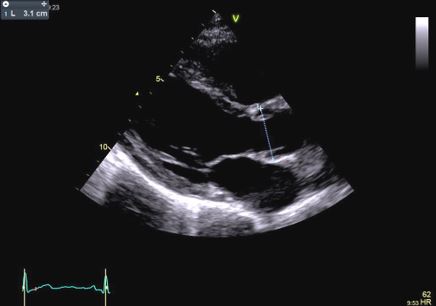

Aortic root diameter measurement should be performed in adults (>15 years) from the parasternal long-axis view during diastole using the L-L convention, preferring 2D measurements (Figure 1)(6).

In our patient transthoracic echocardiography revealed normal diameters of the left ventricle with mild septal hypertrophy (EDD: 51 mm; ESD: 31 mm; IVS: 12 mm; PW 10 mm) with mild enlargement of the right ventricle (mid-cavity diameter: 37 mm), with normal biventricular systolic function. However, TTE revealed a tricuspid aortic valve with dilatation of the aortic root (44 mm, Z-score >2: Z=4.2). Ascending Aorta and aortic arch diameters were normal in absolute values (35 mm and 32 mm, respectively) and when keeping into consideration body size.

After a year, our patient underwent TTE that showed an aortic root dimension of 44 (Figure C), stable in comparison with the previous evaluation, with no modification of ascending aorta measurement and no LV enlargement (Figure A and B). He continues with yearly follow-up, continuing with personalized physical activity previously prescribed.